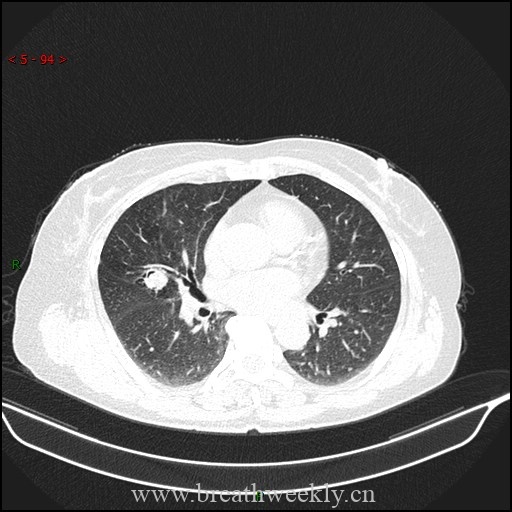

影像学检查

头颅CT除外颅内肿块及脑出血。脑及颈椎MRI(增强)除外CT隐性病灶,但发现右侧胸廓入口处囊性病灶。颈部超声及增强胸部CT:右侧上纵隔囊性占位,位于甲状腺右叶后下方,内见结节性实性成分及上极供血血管。胸部CT示前纵隔预期胸腺位置无异常软组织,提示胸腺脂肪萎缩。

⁹ᵐTc – 甲氧基异丁基异腈甲状旁腺显像:早期及延迟图像均可见甲状腺右叶下方异常摄取灶,摄取位于右上纵隔囊性病灶的实性成分内。

临床过程:因纵隔病灶位置位于甲状腺右叶后下方,术前考虑异位胸腺瘤或异位甲状旁腺腺瘤。CT及超声示无claw sign,排除甲状腺来源。99mTc-Sestamibi显像定位病灶。MG予糖皮质激素及IV免疫球蛋白治疗效果良好;高钙血症予IV补液及cinacalcet治疗。最终行机器人辅助纵隔甲状旁腺腺瘤及胸腺切除术,病理确诊甲状旁腺腺瘤。术后患者恢复良好。